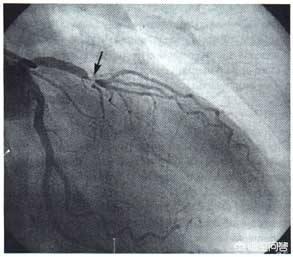

- 造影剤は冠動脈を "照らす":人体の冠動脈は比較的小さく、冠動脈の主幹はわずか5、6ミリ、太い枝の一部は2、3ミリ程度、残りはさらに細い枝で、これらの血管は周囲の組織とつながっており、その手前は骨や筋肉などで覆われている。そこで、冠動脈造影を行う際には、先ほどのカテーテルの中から造影剤を注入し、冠動脈を造影剤で満たします。造影剤はX線不透過性の薬剤で、冠動脈造影の際に冠動脈を "明るく "照らし、冠動脈の分布、大きさ、狭窄や閉塞の有無をはっきり見ることができる。

- DSA(Digital Subtraction Angiography)とは血管を撮影するカメラである:先に述べた冠動脈の写真を撮るための装置がDSAであるが、実はこれもX線検査の一種であり、造影剤を注入しながら様々な冠動脈を多角的に、まさに360度の死角とも言える角度から写真や動画を撮影・記録することができ、これらの写真や動画はCD-ROMに預けることができるので保存や解析が容易である。冠動脈造影が冠動脈疾患を診断するためのゴールドスタンダードであるのは、冠動脈造影がこれほど鮮明な写真やビデオを撮ることができるからである。

- 冠動脈の損傷:冠動脈造影検査では、冠動脈にカテーテルを入れて造影剤を注入する。造影剤は冠動脈の滑らかな内壁に比べて硬くざらざらしている。そのため、冠動脈の内膜が損傷したり、動脈閉塞を起こしたりする危険性があり、生命を脅かす。

冠動脈造影検査は、大腿動脈の位置から針を刺し、冠動脈の位置までチューブを通し、ヨード造影剤を打ち込んで冠動脈を映し出し、冠動脈の先天性疾患、アテローム性動脈硬化症、動脈瘤、動脈奇形などを診断するもので、その多くは内腔の狭窄をもたらすアテローム性動脈硬化症である。狭窄の程度を評価することができ、心筋梗塞を伴う重度の狭窄の場合は、治療目的で狭窄した内腔を広げて血流を回復させるためにステントを直接挿入することができる。